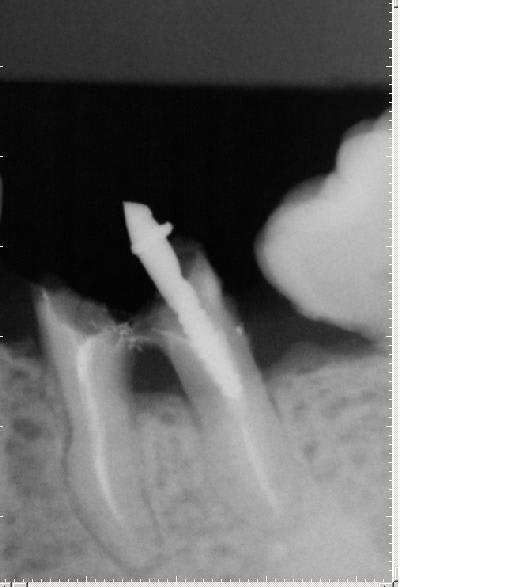

Ps: on peut noter le tartre encore présent sur la face mesiale de la 38 versée/mésialée.... on fera ça + tard lors de la litho/laser. Ca prouve bien que malgré tous les handicaps cumulés par ces 2 dents le seul traitement local a déjà été trés efficace.

oui on voit bien la corticalisation preuve que tout est au repos au niveau du parodonte profond ....